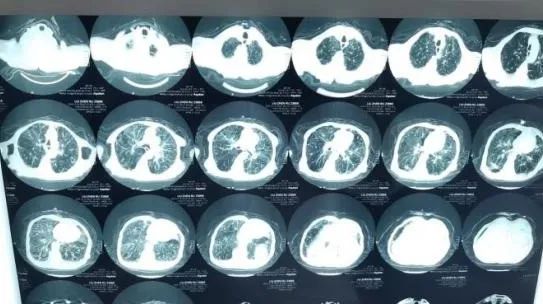

10月16日,省荣康医院内科接诊一名男性患者,86岁,突发右侧肢体无力、言语不能2小时。患者入院后,当天接诊的李梅医生立即通知来自安庆市第一人民医院神经内科驻点帮扶的王建飞医师,评估患者既往有脑梗塞、高血压病史,平素拄拐行走,现神志清楚,右侧上肢肌力0级,右侧下肢肌力2级,失语,右侧巴氏征阳性,NIHSS评分10分。初步诊断考虑为急性脑卒中,发病2小时,有可能需要进行静脉溶栓治疗。于是王建飞医师立即启动绿色通道,护士迅速完成生命体征的监测、测血糖、采血送检、完善心电图,内科储德文主任第一时间联系检验科,争取快速完成血检。王建飞医师则陪同患者前往影像科行头颅+胸部CT检查以及磁共振脑血管评估,急查头颅CT提示:1.多发腔隙性脑梗塞;2.老年性脑改变。胸部CT提示:1.肺气肿;2.两侧胸腔积液;3.心包少量积液。头颅MRA提示:双侧大脑中动脉M2段纤细。